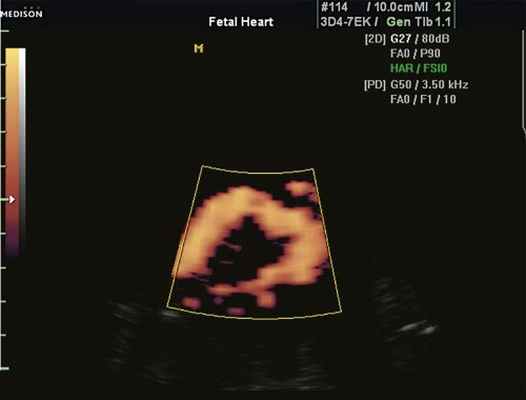

Рис. 1. Восходящий отдел, дуга и нисходящий отдел аорты плода в режиме энергетического допплера в норме.

Согласно "теории дуктальной ткани" коарктация аорты возникает в результате миграции гладких мышечных клеток протока в предуктальную аорту, с последующей констрикцией и сужением просвета аорты [4]. При формировании коарктации аорты в области перешейка сохраняется сужение различной протяженности и формы (рис. 2, 3). Наиболее часто это проявляется в виде локальной перетяжки, выше или ниже которой диаметр аорты сохраняется в норме.

Рис. 2. Ультразвуковое исследование восходящего отдела, дуги и нисходящего отдела аорты. Стрелкой указано место сужения.